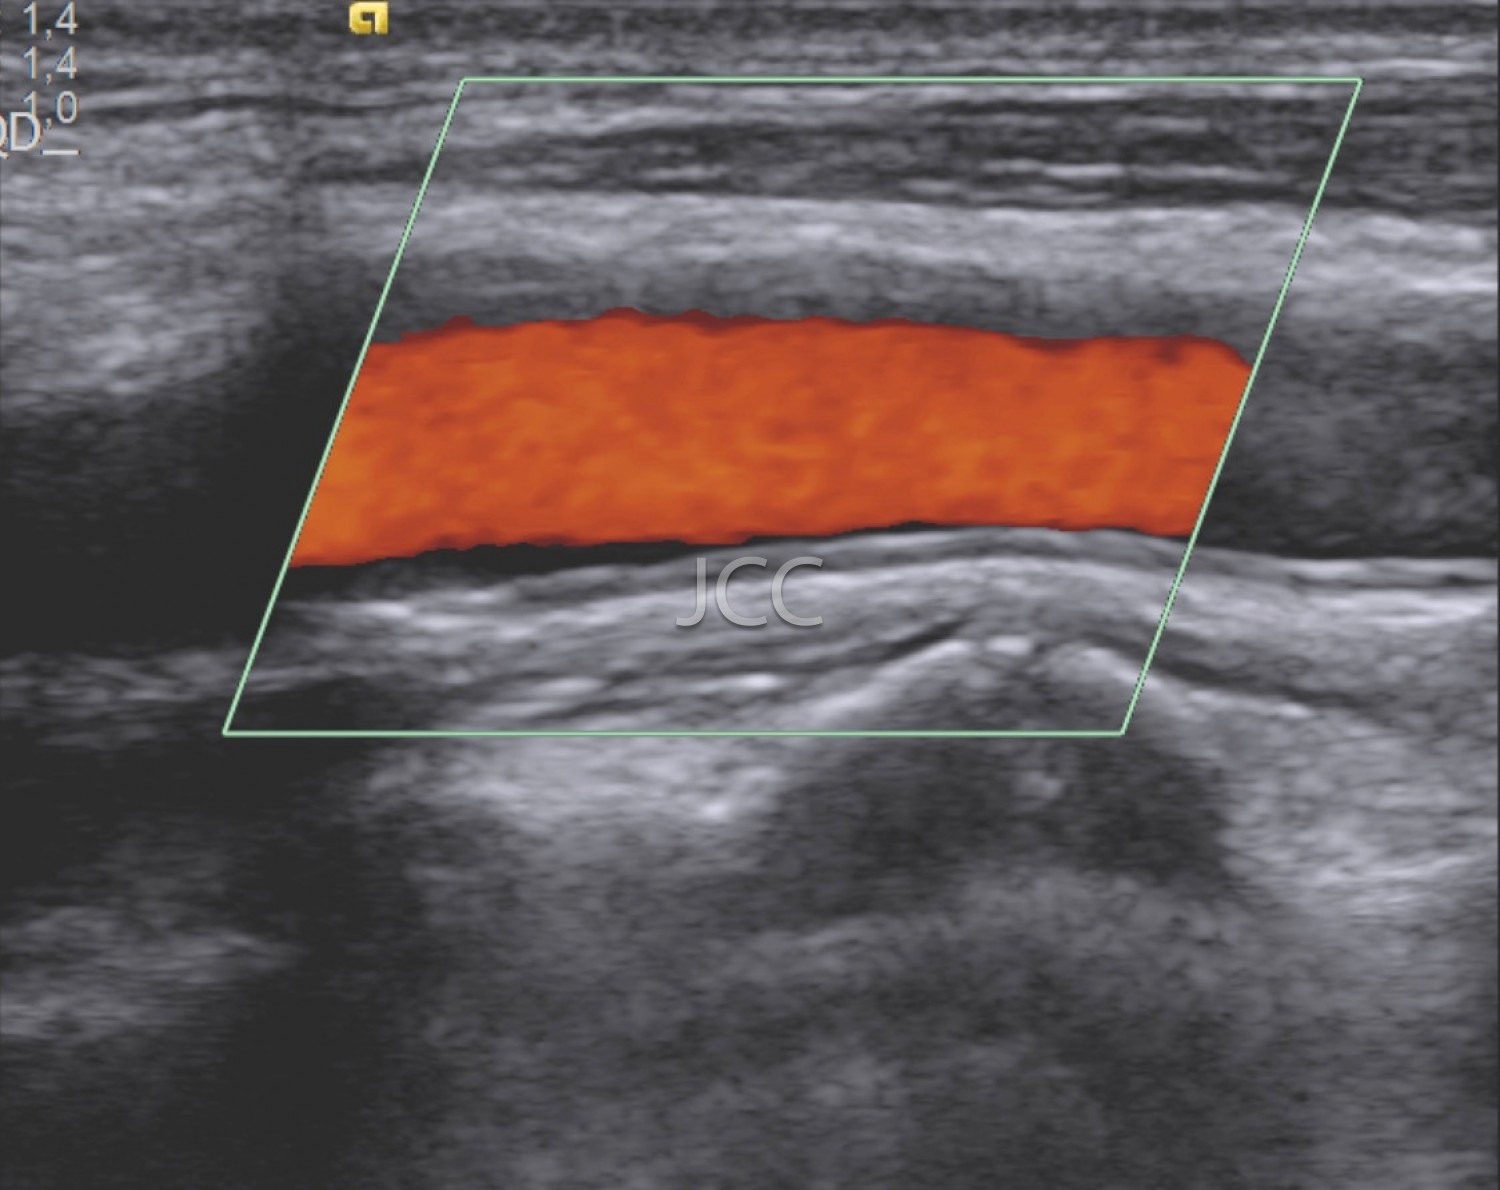

Ecografia - Ecografia Vascular - Doppler

A Ecografia constitui um método mais acessível permitindo de modo simples e rápido a avaliação dos órgãos do corpo humano incluindo o fígado, vias biliares, vesícula, pâncreas, rins, bexiga e próstata, bem como órgãos de menores dimensões como a tiróide, parótidas e estruturas musculares.

Constitui uma óptima técnica para guiar a realização de biópsia. Quando associada ao Doppler permite o estudo das estruturas vasculares arteriais e venosas de modo dinâmico.